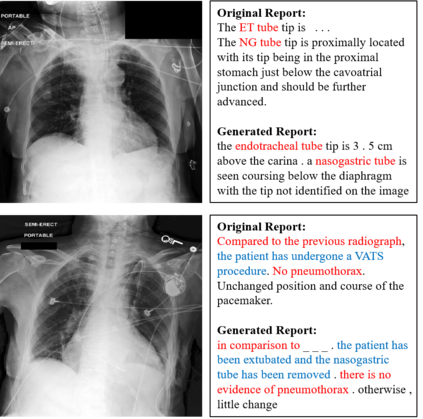

Recently a number of studies demonstrated impressive performance on diverse vision-language multimodal tasks such as image captioning and visual question answering by extending the self-attention based Transformer architecture with multimodal pre-training objectives. Despite its huge potential, vision-language multimodal pre-training in the medical domain has only recently received attention, and only demonstrated improved diagnosis accuracy of vision-language pre-trained models. In this work we explore a broad set of multimodal representation learning tasks in the medical domain, specifically using radiology images and the unstructured report. We propose a new model which adopts a Transformer based architecture combined with a novel multimodal attention masking scheme to maximize generalization performance for both vision-language understanding task (e.g., diagnosis classification) and vision-language generation task (e.g., radiology report generation). By rigorously evaluating the proposed model on four downstream tasks with three radiographic image-text datasets (MIMIC-CXR, Open-I, and VQA-RAD), we empirically demonstrate the superior downstream task performance and generality of our model against various baselines including task specific architectures. In addition, we qualitatively analyze our model by showing the results of retrieved image-report pairs, the attention map visualization, and generated reports. Our proposed multimodal pre-training model could flexibly adapt to multiple downstream tasks of vision-language understanding and generation with a novel self-attention scheme. We believe that our approach can provide the basis for a wide range of interpretations of vision-language multimodal in the medical domain.